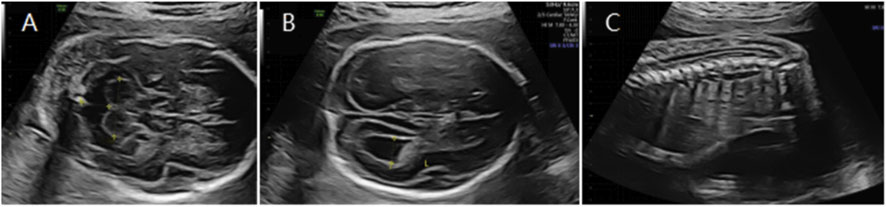

Figure 4

Ultrasound images labeled A, B, and C. Image A shows a cross-sectional view with various anatomical structures. Image B highlights a circular formation, possibly a head. Image C illustrates a series of vertical lines, suggesting spinal vertebrae.

Figure 4. (A) Transverse ultrasound section showing the fetal cerebellum; transverse cerebellar diameter measured 20.2 mm (<–3.0 SD for gestational age). (B) Axial ultrasound view in the transventricular plane demonstrating bilateral ventriculomegaly, with atrial widths of approximately 8.9 mm (left) and 10.8 mm (right). (C) Sagittal ultrasound view showing a low-lying conus medullaris.